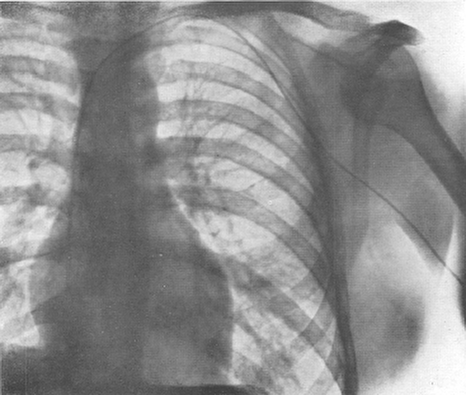

سرآغاز مطالعه تهاجمي داخل قلب و عروق يا همان آنژيوگرافي و كاتتريزاسيون قلب٬ ريشه در شهامت و شجاعت يك پزشك جوان آلماني دارد.